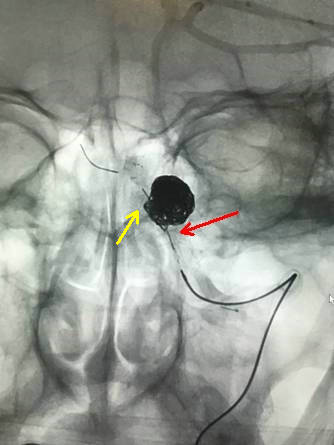

术中栓塞情况(黄箭头示支架marker,红箭头示弹簧圈)